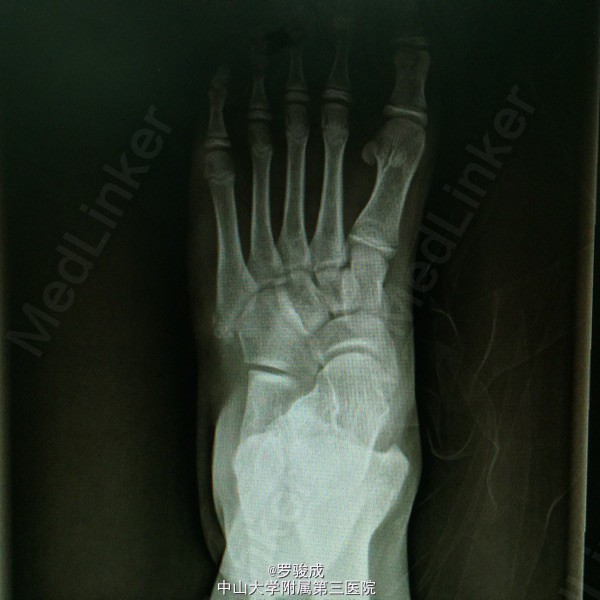

左足内侧疼痛2年余 两年余前运动后出现左足内侧疼痛,伴胀痛,无放射痛,无足部麻木。近来症状加重,遂前来我院就诊,X线提示左足副舟骨综合症。

左足内侧弓副舟骨表面硬性突起,无红肿,皮肤温度无升高,压痛明显。左足神经血运及感觉良好

诊断为左足副舟骨综合症。 行左足副舟骨清理融合术

足副舟骨综合症是一种先天性疾病,是舟骨结节部第二化骨中心的先天异常,在舟骨结节处形成一个独立的副骨。 足内侧隆起,久站或行走较长时, 感足底内侧疼痛。